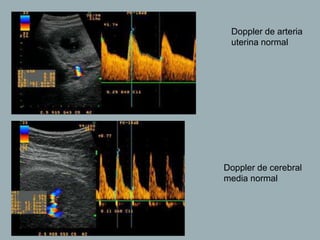

Doppler de arteria

uterina normal

Doppler de cerebral

media normal

Doppler de arteria uterinanormal Doppler de cerebral media normal